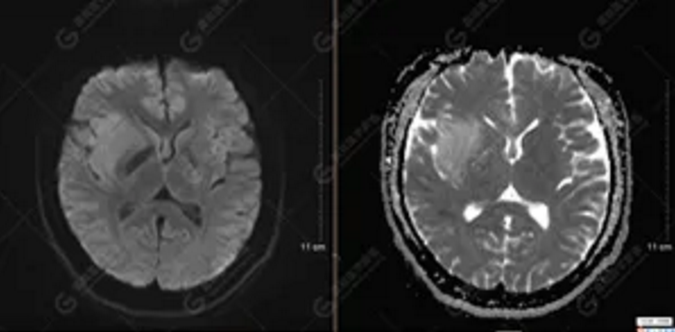

【MRI平掃及增強(qiáng)檢查所見(jiàn)】右側(cè)額顳島葉、右側(cè)海馬及右側(cè)基底節(jié)區(qū)見(jiàn)一團(tuán)塊狀異常信號(hào)影,累及右側(cè)下丘腦及視交叉,大小約5.1cm×4.5cm×4.3cm,呈長(zhǎng)T1長(zhǎng)T2信號(hào),F(xiàn)LAIR序列呈等、稍高信號(hào),DWI序列呈稍高信號(hào),ADC圖高信號(hào),增強(qiáng)后無(wú)明顯強(qiáng)化;病灶周?chē)?jiàn)片狀長(zhǎng)T1長(zhǎng)T2水腫信號(hào)影,F(xiàn)LAIR序列呈高信號(hào),病灶內(nèi)見(jiàn)右側(cè)大腦中動(dòng)脈穿行。余腦實(shí)質(zhì)內(nèi)未見(jiàn)局灶性信號(hào)異常,增強(qiáng)后未見(jiàn)異常強(qiáng)化。右側(cè)側(cè)腦室輕度受壓,余腦室、腦池大小、形態(tài)均正常,中線(xiàn)結(jié)構(gòu)居中